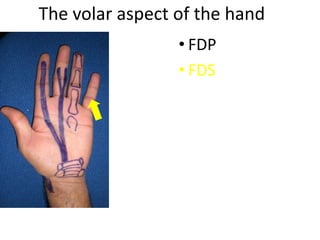

- Naming the bones, joints, tendons, nerves and skin landmarks of the hand and wrist.

- It describes flexor tendon zones, extensor compartments, and pulley system anatomy.